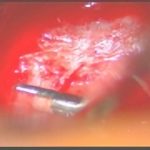

術中写真

摘出 後